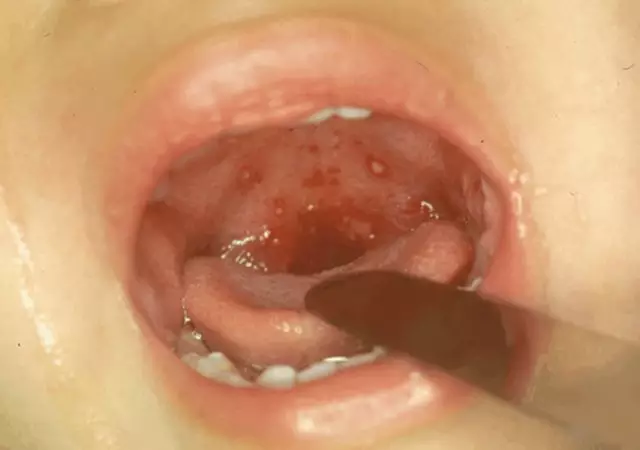

2、皰疹性咽峽炎:高熱伴有咽喉痛,頭痛,厭食,并常有頸,腹和四肢疼痛.在嬰兒期常發生嘔吐和驚厥,生病2日內口腔粘膜出現少數灰白色皰疹。

2、皰疹性咽峽炎:發熱后同時或第2天口腔內出現皰疹